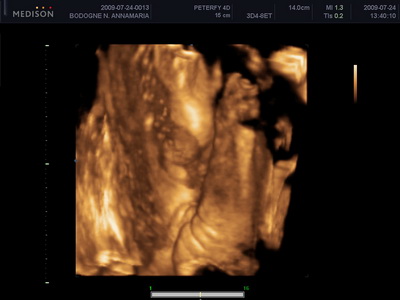

Mi megvagyunk, növögetünk ezerrel. Pénteken voltunk 4d-n, minden rendben van. Lilike most már biztos hogy Lilike, nem szégyenlős a drágám, rendesen bepucsított és szép kis hurija is van. 1000g-nak mérték és azt mondta a doktornő, hogy készüljünk, hogy szép nagy baba lesz. Nem a súlya lesz óriási, hanem szép hosszú lesz, lehet hogy 58-60 cm :lol: Mondjuk erre számítottunk mert mi se vagyunk alacsonyak :lol: Egyébként tiszta apja a kis drága. Nagy csókos szája van és kis kerek arcocskája. Teljesen beleszerettem :lol: Még puszit is küldött nekünk a kis husi szájával. Teszek fel pár képet nektek.

Kis csókos szájú

Vitathatatlan nunis

Nyitott szemmel